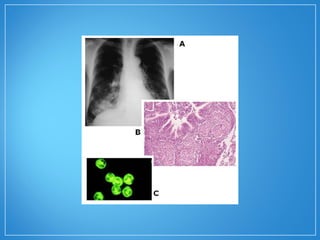

• O padrão citoplasmático (cANCAcANCA) na imunofluorescência

indireta é um marcador do anticorpo dirigido à proteinase-

3, protease presente nos grânulos azurófilos dos

neutrófilos, e o padrão perinuclear (P-ANCAP-ANCA) é um

marcador do anticorpo antimieloperoxidase, enzima

presente nos lisossomos dos neutrófilos. O padrão

citoplasmático relaciona-se com a granulomatose de

Wegener, com especificidade de até 90%. O padrão

perinuclear correlaciona-se a outras vasculites, como a

poliangeíte microscópica. Os estudos iniciais mostraram

sensibilidade e especificidade acima de 90% na doença

em atividade.

• As manifestações histológicas da

granulomatose de Wegener incluem

necrose parenquimatosa, vasculite e

inflamação granulomatosa.

• O padrãocitoplasmático (cANCAcANCA) na imunofluorescência indireta é um marcador do anticorpo dirigido à proteinase- 3, protease presente nos grânulos azurófilos dos neutrófilos, e o padrão perinuclear (P-ANCAP-ANCA) é um marcador do anticorpo antimieloperoxidase, enzima presente nos lisossomos dos neutrófilos. O padrão citoplasmático relaciona-se com a granulomatose de Wegener, com especificidade de até 90%. O padrão perinuclear correlaciona-se a outras vasculites, como a poliangeíte microscópica. Os estudos iniciais mostraram sensibilidade e especificidade acima de 90% na doença em atividade.

• As manifestaçõeshistológicas da granulomatose de Wegener incluem necrose parenquimatosa, vasculite e inflamação granulomatosa.